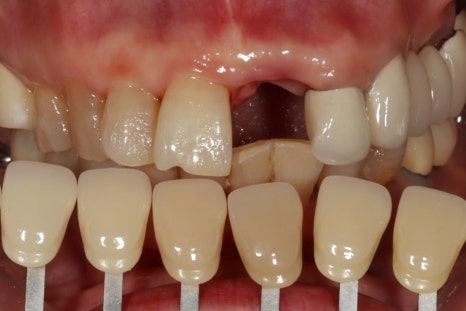

아래 앞니 신경치료 및 크라운 케이스

위 앞니 발치 즉시 임플란트, 크라운 케이스